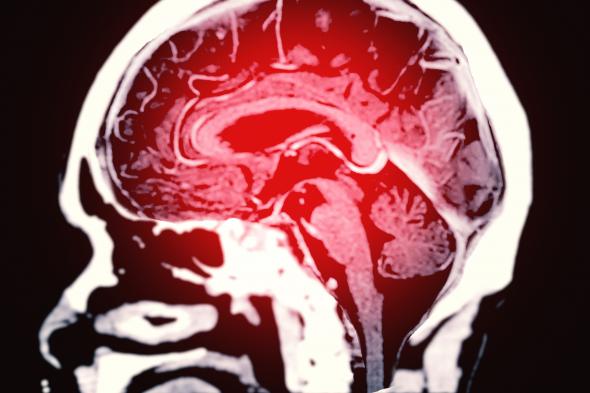

Una imagen de archivo de un escáner cerebralGetty Images